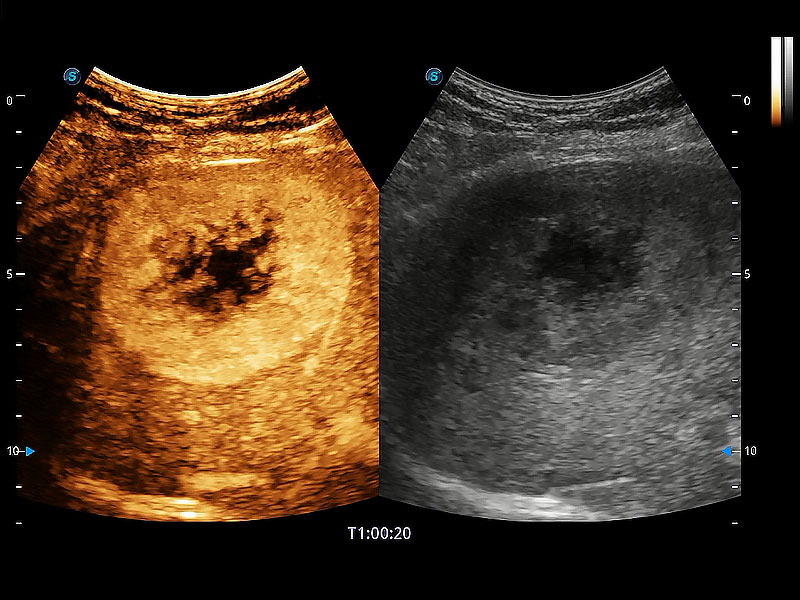

操作简便,无需高频度外力作用即可真实反映组织的形变,快速评估肿瘤良恶性。

非线性融合造影成像充分利用谐波和基波信号,为难以观察的血流进行增强显像。可用于线阵、凸阵、微凸阵、相控阵探头。

为精细结构及组织边缘提供高清晰度的图像和更大的成像视野。帮助减轻医生的用眼疲劳,快速精准获得测量的数据。